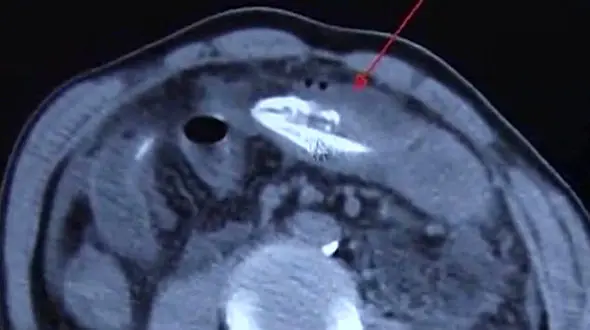

حوادث رکنا: مرد چینی که به طور اشتباهی و با شلیک تیرکمان جانش را به خطر انداخت توسط پزشکان از مرگ گریخت.